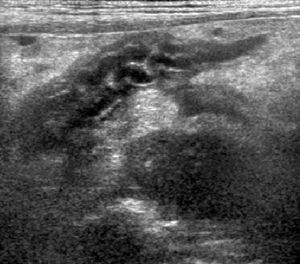

Pancreatitis is a common consideration in dogs and in an increasing number of cats presented for vomiting, anorexia, lethargy, or abdominal pain.